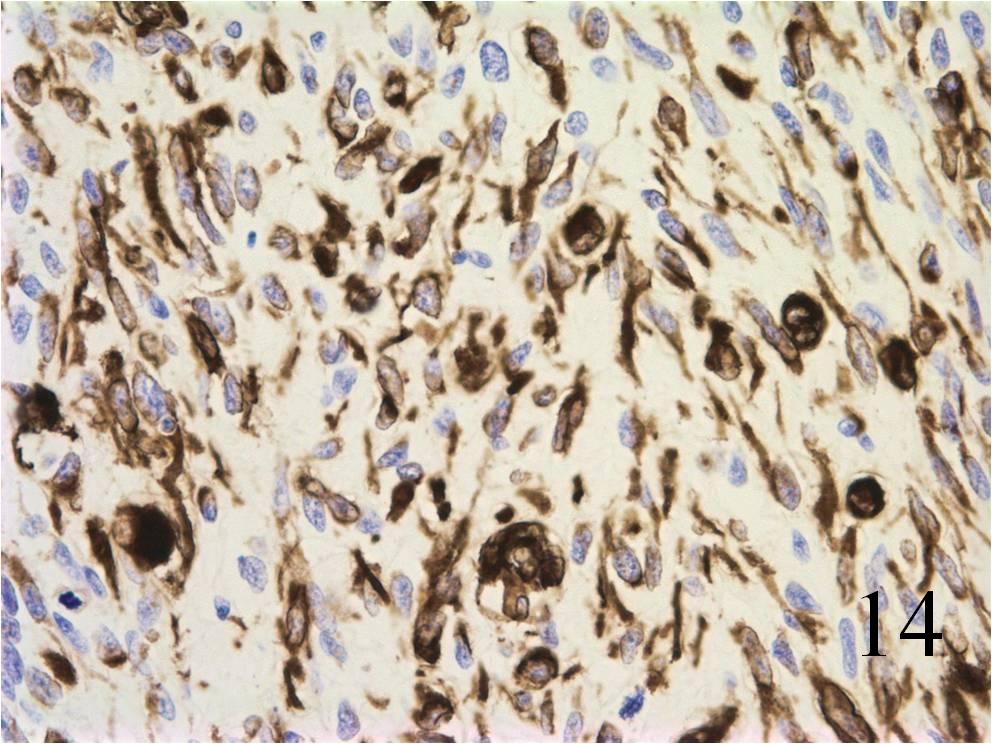

Microscopic

- Embryonal:

- Small round blue cells (Fig. 12-15)

- Round, oval, polygonal cells

- Fibrotic/myxoid stroma

- Rhabdomyoblast: well differentiated will have cross striations

Immunohistochemistry

- Vimentin positive; Keratin negative

- Actin variable; perhaps minor scant staining

- S-100 negative